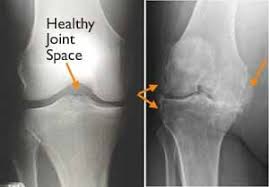

The patella or kneecap is seen sitting in front and to the left of the femur. A lateral view x ray shows the knee from the side. The image here is a front to back view of the knee joint also called the ap view.

Find x ray of knee stock images in hd and millions of other royalty free stock photos illustrations and vectors in the shutterstock collection. Add to likebox 127713977 wheelchair icon simple style. X ray image of right knee ap and lateral view showing total knee arthroplasty and fractures of the tibial plateau with. This x ray shows a healthy joint with nice sharp well defined edges at the joint margins.